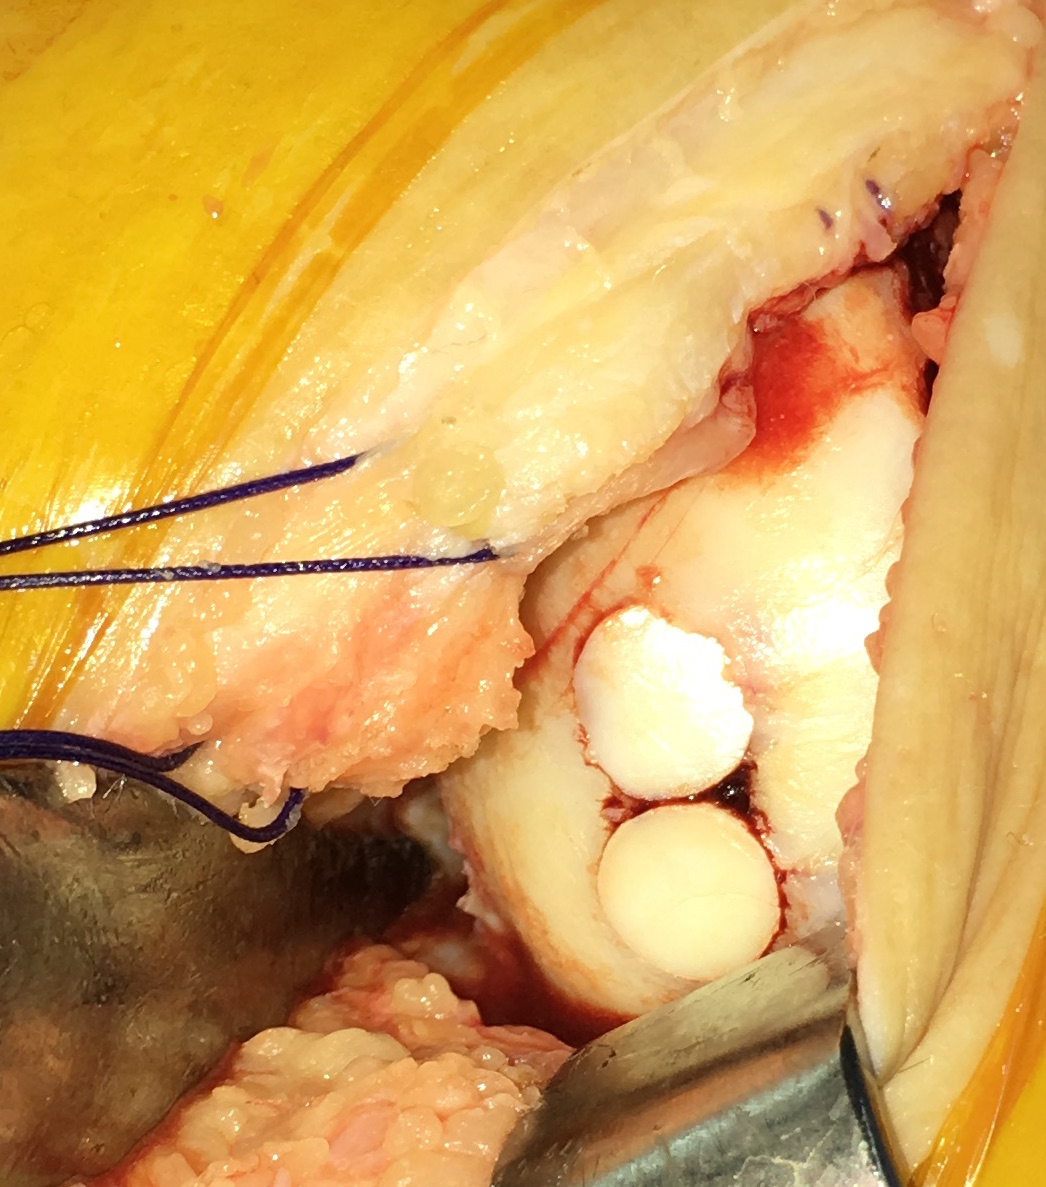

There are several surgical options described for osteochondral defects of the knee. The aim of our study was to analyze a series of patients treated with mosaicplasty with an average of 8 years follow-up.            Sixty-two patients with osteochondral defects of the knee who underwent mosaicplasties between 2001 and 2014 were included in the study with minimum follow-up of 2 years. Patients were evaluated using the Lysholm score, International Knee Documentation Committee Score (IKDC) and Kellgren-Lawrence radiographic scale.            Forty-five were men and seventeen women with an average age of 36 years old. Mosaicplasties were 45 in the medial condyle, 12 lateral condyle, 12 trochlea and 3 combined. Forty-two patients had isolated mosaicplasties and 20 patients presented associated surgical procedures (osteotomy, ACL reconstruction, meniscectomy). The mean results of the Lysholm score were 80.1 and IKDC was 66.7. There were no significant differences among the Lysholm and IKDC scores between these two groups. In 30 patients evaluated with radiography a satisfactory inclusion of the bony block was observed.            We believe that mosaicplasty is a procedure with a high degree of satisfaction with good functional results in patients with focal lesions of articular cartilage that may or may not be associated to other surgical procedures.